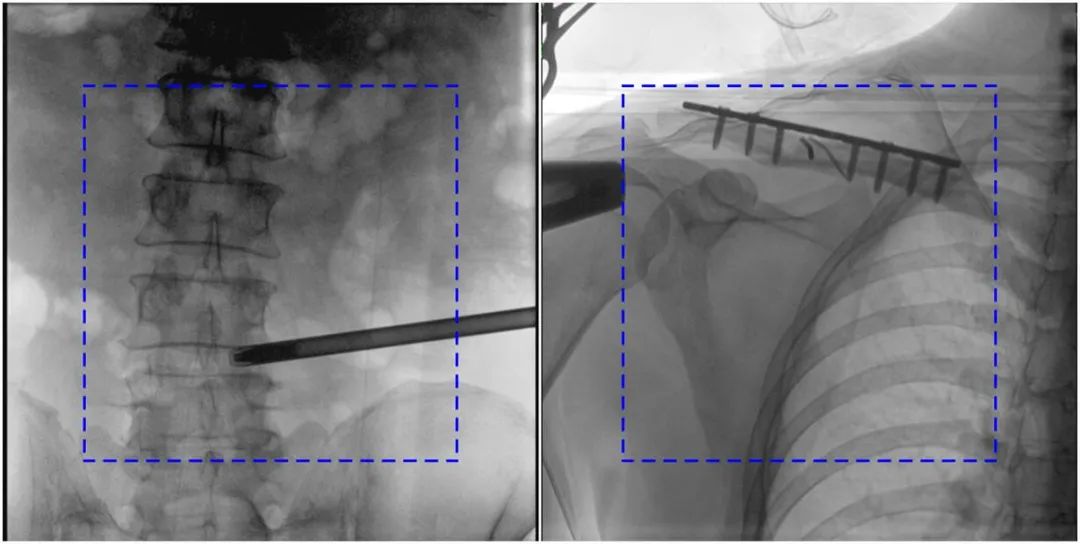

PLX119C臨床圖像與傳統(tǒng)圖像對比

注:藍(lán)色虛線內(nèi)為傳統(tǒng)21CM×21CM平板的成像區(qū)域。